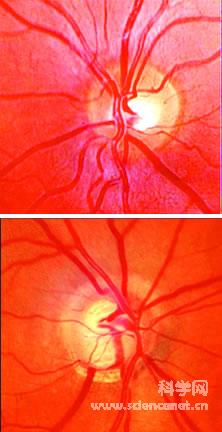

与健康的眼球相比(上图),青光眼(下图)的视神经(白色区域)受到了损伤。